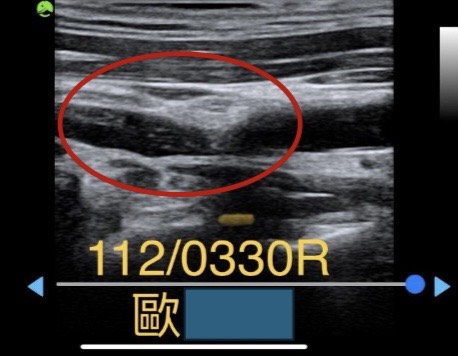

112/03/30 頸動脈超音波檢查1

檢查發現,右側頸動脈有一斑塊栓塞嚴重(紅色框處),只剩1/5的血液能通過,導致供應腦部血液不足,腦部常處在缺氧狀態,引發胸悶、頭暈、精神不佳、嚴重失眠的狀況。

院長立即開立親自調配的精準活血化瘀的「清脈通竅方」,來疏通快塞住的頸動脈,避免中風的危機。